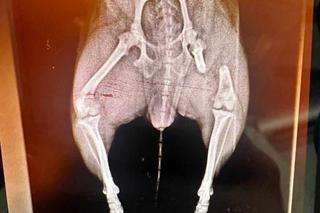

Mieszkanka Raciborza w piątkowy wieczór około godziny 20:00 przechodziła razem ze swoim 7-letnim wnuczkiem i psem przez park im. Miasta Roth, kiedy podbiegł do nich agresywny czarno-biały pies w typie amstaffa. Duży pies rzucił się do ataku i pogryzł zaledwie 2-letnią suczkę rasy chihuahua o imieniu Milka. Suczka w bardzo ciężkim stanie trafiła do kliniki weterynaryjnej, gdzie rozpoczęto walkę o jej życie. Do tej pory znajduje się pod opieką specjalistów i wciąż nie wiadomo, czy jej stan się poprawi.